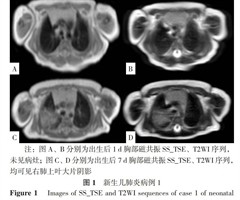

新生儿肺炎磁共振SS_TSE与改良腹部T2WI序列的特征分析

【摘要】 背景 目前临床普遍使用X线检查甚至螺旋CT诊断新生儿肺炎,导致医源性辐射伤害;而应用磁共振诊断新生儿肺炎可减少医源性辐射伤害,但相关研究较少。目的 基于1.5 T低场强磁共振单次激励快速自旋回波(SS_TSE)序列与改良腹部T2W...